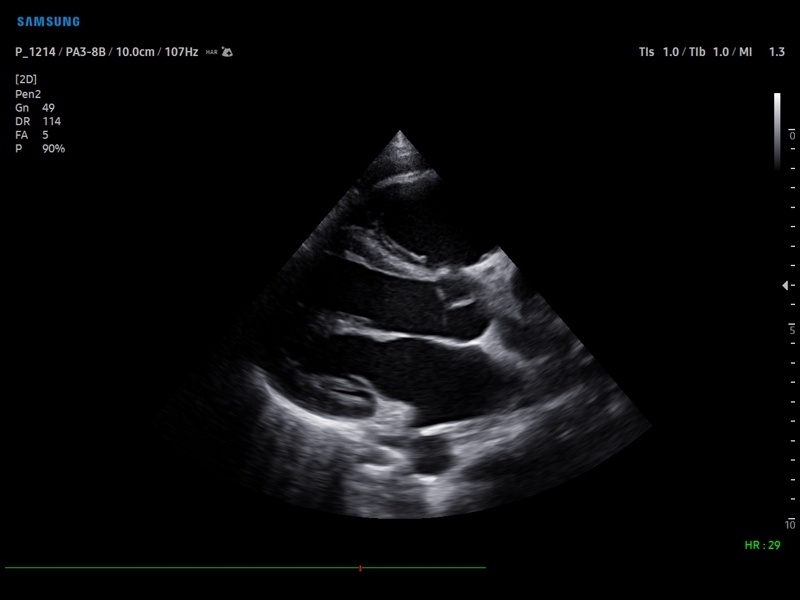

Ультразвуковой сканер V8-RUS является экспертным классом (премиальный уровень) и производится компанией Samsung Medison. Сканер V8 обеспечивает превосходное качество изображения благодаря использованию технологии Crystal Architecture™, которая включает в себя передовое аппаратное обеспечение, монокристальную технологию изготовления датчиков и сложную программную обработку ультразвуковых лучей.

Samsung Medison V8 представляет собой современную ультразвуковую систему, в которой воплощен многолетний опыт компании Samsung в создании эргономичного и интеллектуального диагностического оборудования. Система оснащена передовыми инструментами автоматизации, которые значительно упрощают рабочий процесс и повышают эффективность исследований.

• Кардиология